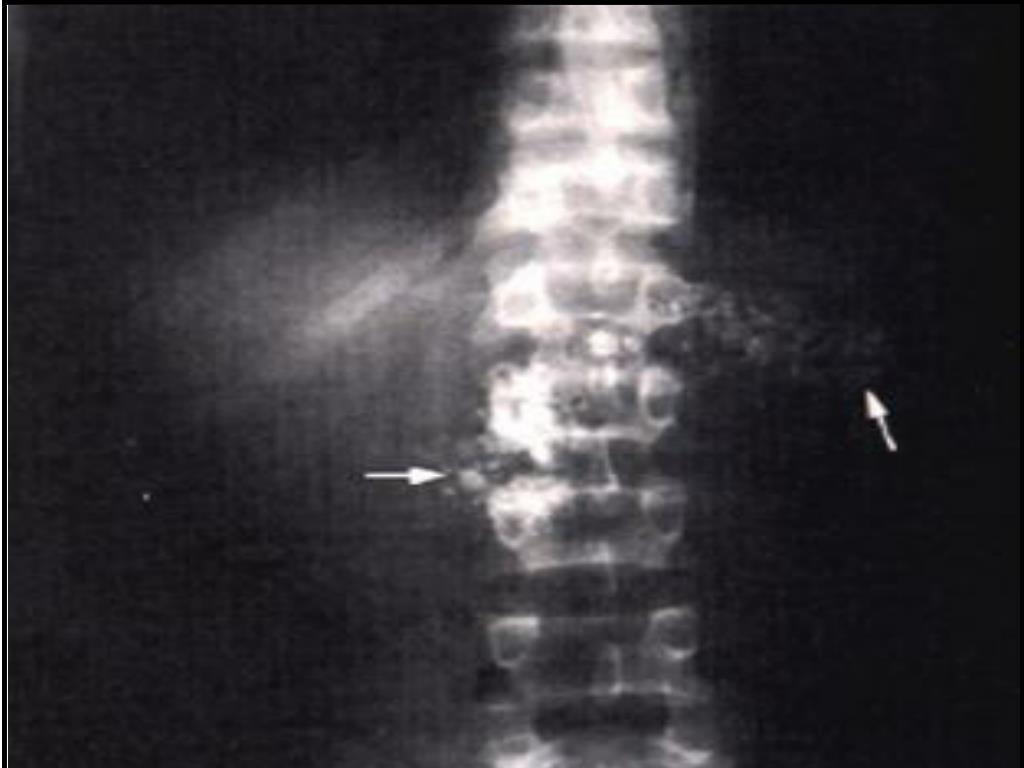

Qual o diagnóstico?

Pancreatite crônica: o normal é não ver o pâncreas no raio-x, quando visualiza é pela presença de calcificações